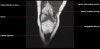

무릎 관절의 MRI 단면영상2016-08-31카테고리 106원본 보기1. Sagittal section 2. Coronal section 3. Axial section ← 이전 글전방 족근관증후군(Anterior tarsal tunnel syndrome) : 발등이 꽉 끼는 구두를 신은 후부터 발등을 누르면 아프고 엄지와 검지 발가락 사이가 저려요다음 글 →흉곽출구증후군(Thoracic outlet syndrome) : 팔이 아프고 감각이 떨어지면서 저려요같은 카테고리 글2017-06-10톰슨 검사(Thompson test) : 아킬레스건 파열을 조사하는 테스트2017-06-09Apley 압박 검사(Apley compression test) : 반월상 연골 손상을 조사하는 테스트2017-06-08맥머레이 시험(McMurray test) : 반월상 연골 손상을 조사하는 테스트← 전체 글로 돌아가기